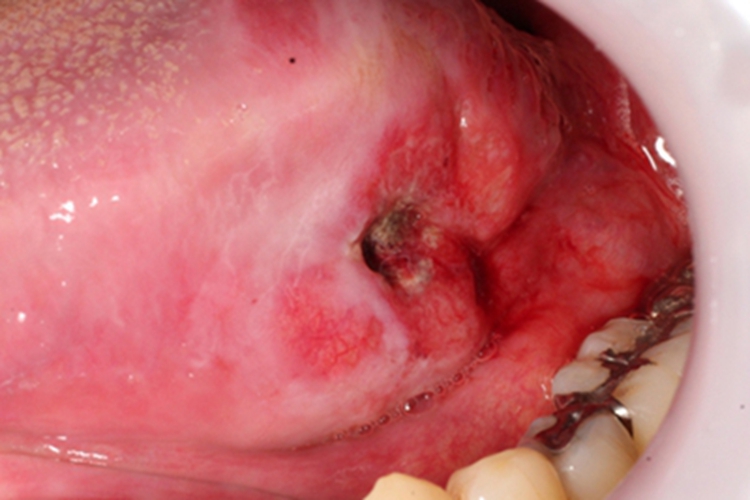

舌癌患者局部可见有一块溃疡,溃疡中央凹陷,久不能愈合,周围红肿,有血丝,表面有黑色坏死。患者自觉舌头疼痛剧烈,难以进食。